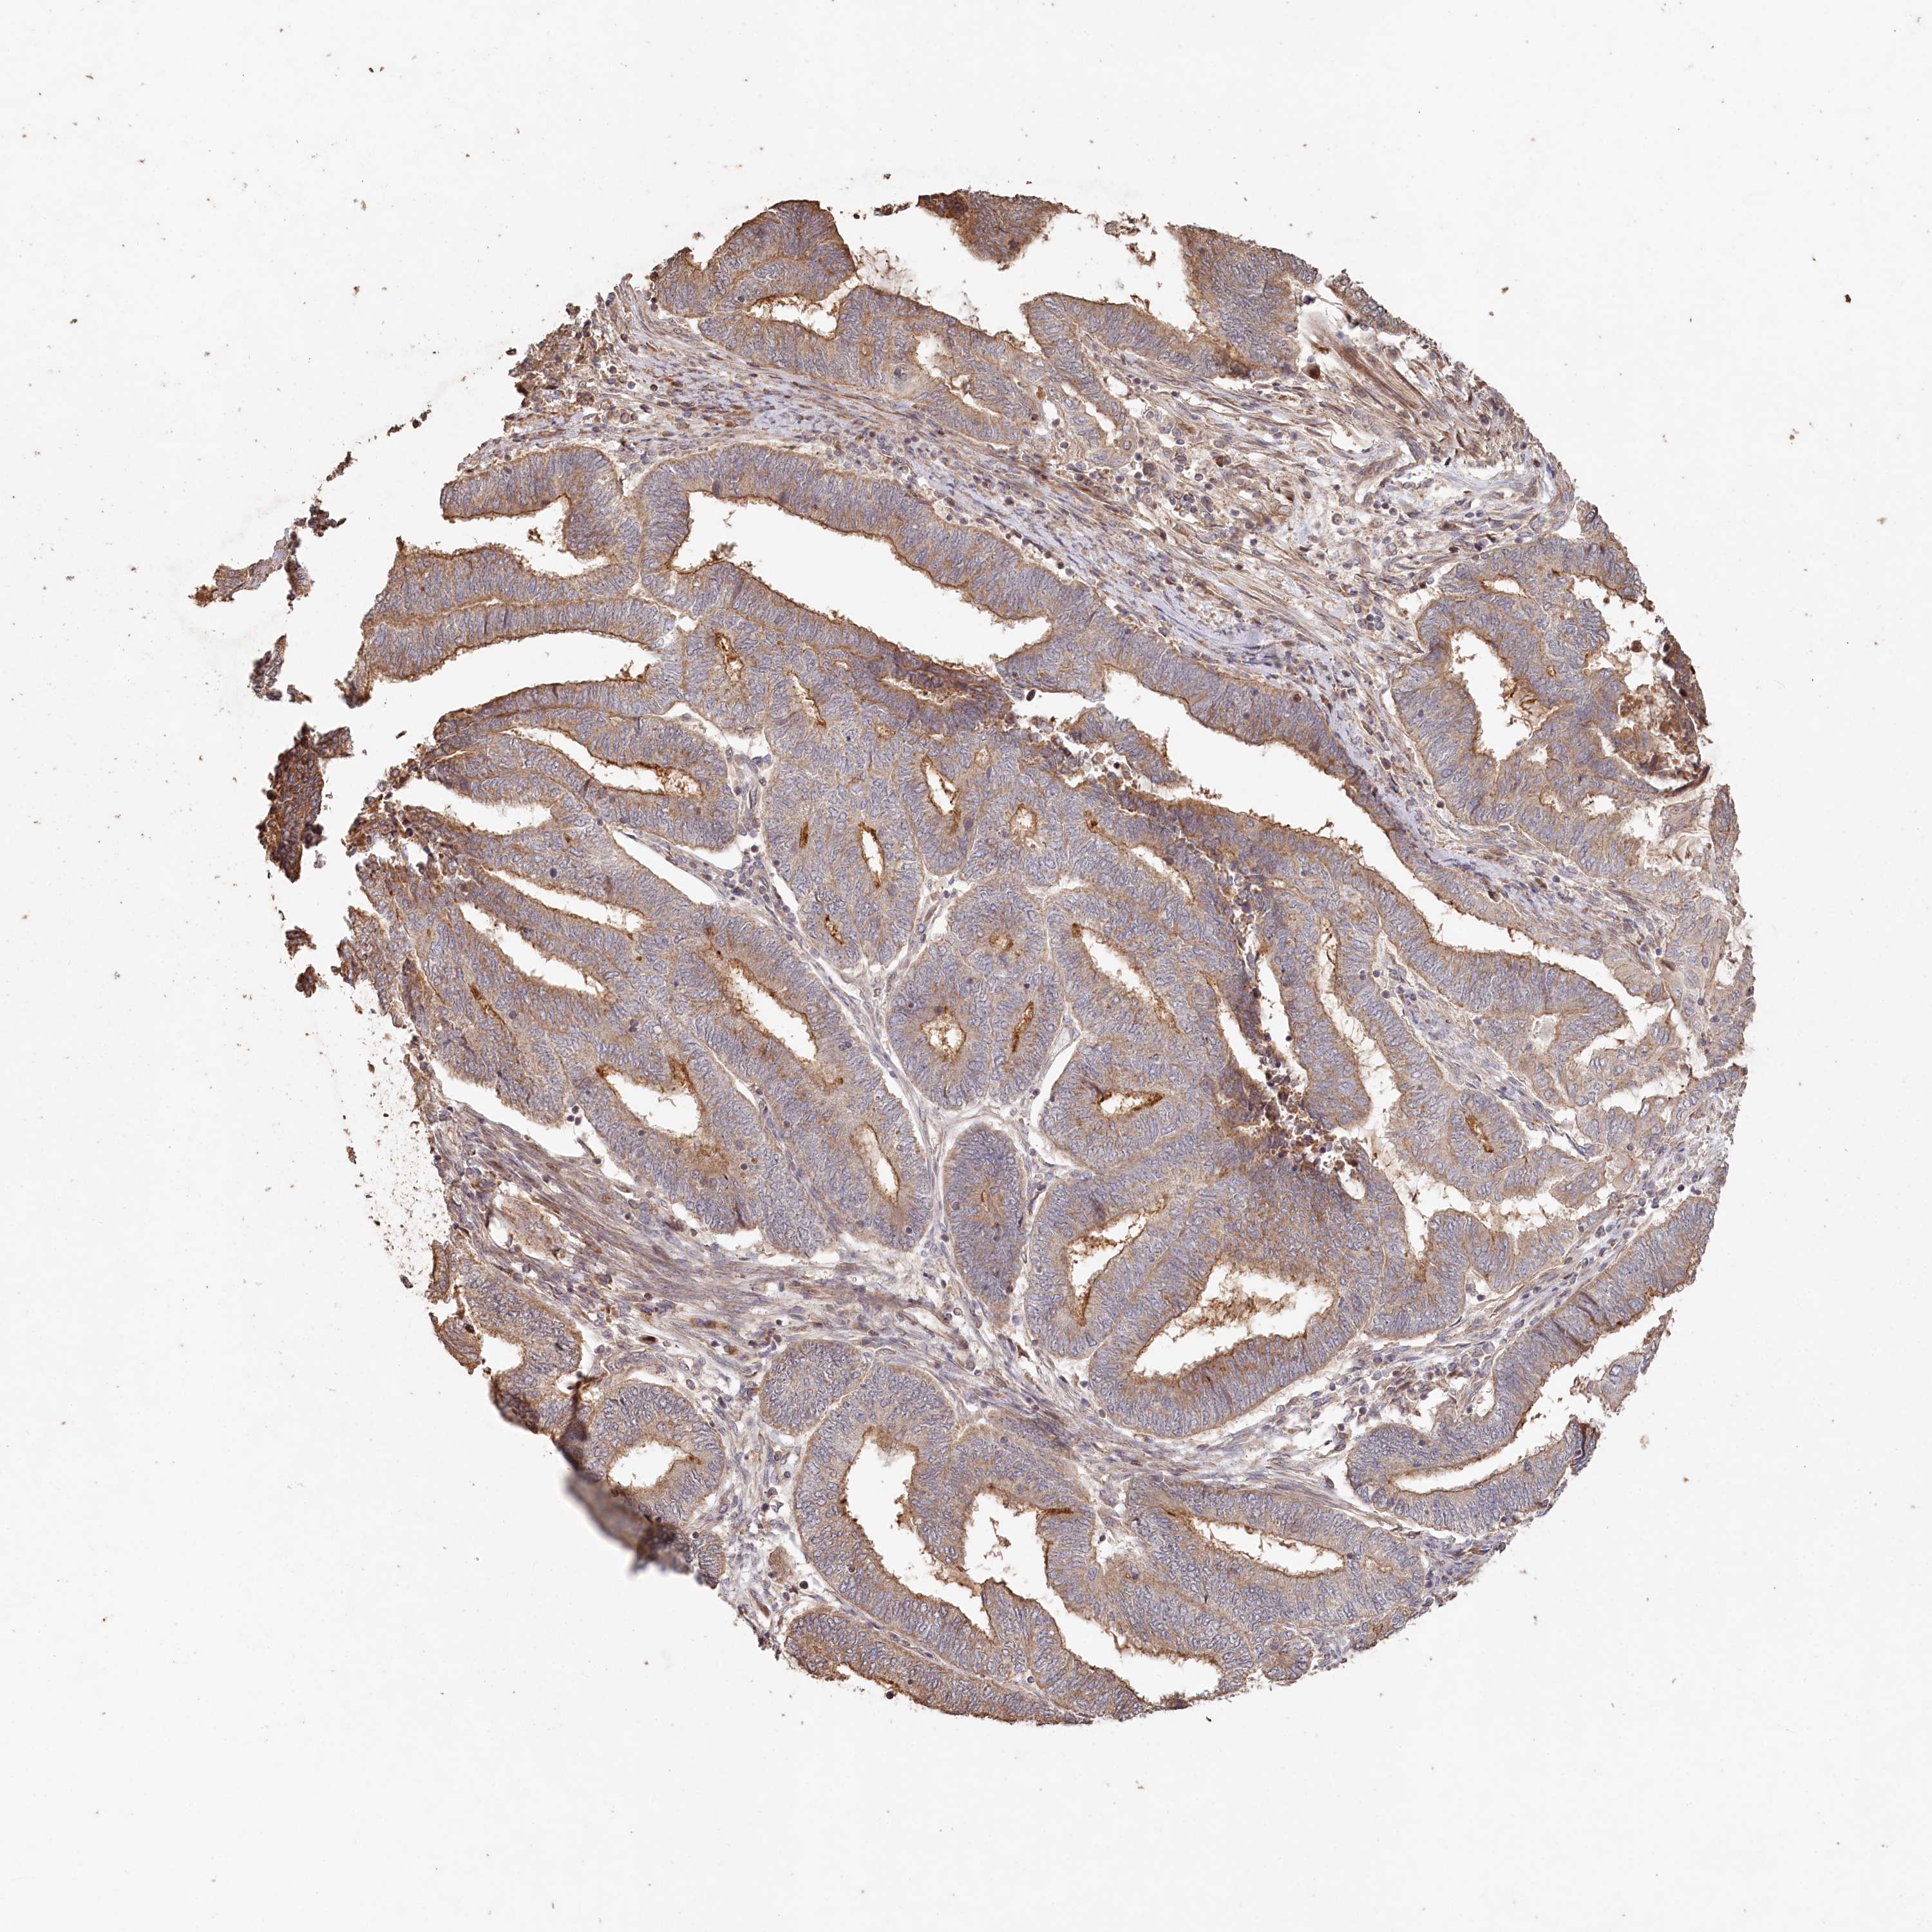

ENDOMETRIAL CANCER - Protein expressioni

A mouse-over function shows sample information and annotation data. Click on an image to view it in a full screen mode. Samples can be filtered based on level of antibody staining by selecting one or several of the following categories: high, medium, low and not detected. The assay and annotation is described here.

Note that samples used for immunohistochemistry by the Human Protein Atlas do not correspond to samples in the TCGA dataset.

Antibody stainingi

Antibody staining in the annotated cell types in the current human tissue is reported as not detected, low, medium, or high, based on conventional immunohistochemistry profiling in selected tissues. This score is based on the combination of the staining intensity and fraction of stained cells.

Each image is clickable and will lead to virtual microscopy that enables deeper exploration of all samples and also displays staining intensity scores, fraction scores and subcellular localization as well as patient and tissue information for each sample.

Antibody HPA038547

Antibody HPA038548

Staining

High

Medium

Low

Not detected

Intensity

Strong

Moderate

Weak

Negative

Quantity

>75%

75%-25%

<25%

None

Location

Nuclear

Cytoplasmic/membranous

Cytoplasmic/membranous,nuclear

Adenocarcinoma, NOS